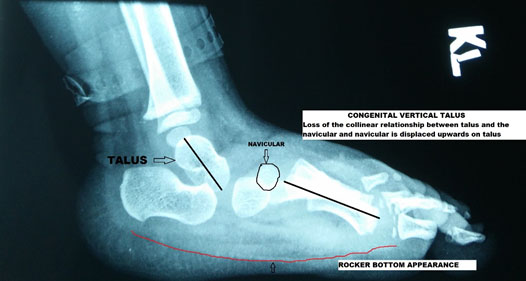

Congenital Vertical Talus (CVT- Rocker bottom Foot)

CVT is an entity where the foot arch is reversed with the convexity of the feet plantar wards. This appearance is the rocker bottom foot. It is due to the loss of the relationship of the bones of the mid-foot to the hindfoot

It is associated with genetic syndromes like myelomeningocele & arthrogryposis, and the functional outcome of the child is primarily determined by the associated anomalies. Symptoms include difficulty to walk and excessive heel contact, and the front of the foot has limited contact to the floor. X rays (as shown in the picture above) aid the diagnosis and can be helpful in planning treatment.